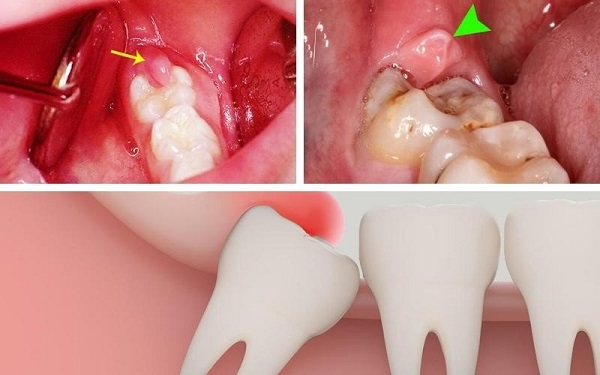

- Viêm lợi trùm: Khi răng khôn mọc, mô nướu phát triển và phủ lên một phần răng khôn đang nhú lên. Nếu răng khôn mọc thẳng, tình trạng sưng nướu răng sẽ kết thúc sau vài ngày. Tuy nhiên, nếu răng khôn mọc lệch, cơn đau này sẽ lặp đi lặp lại và việc sử dụng thuốc chỉ giúp giảm đau tạm thời.

- Sưng nướu răng khôn: Khi răng khôn mọc, sưng nướu và đau nhức xương hàm rất dễ mắc phải. Vị trí của răng khôn ở cuối hàm làm cho việc vệ sinh khó khăn, tạo điều kiện cho vi khuẩn tấn công, gây sưng mủ và viêm nhiễm.